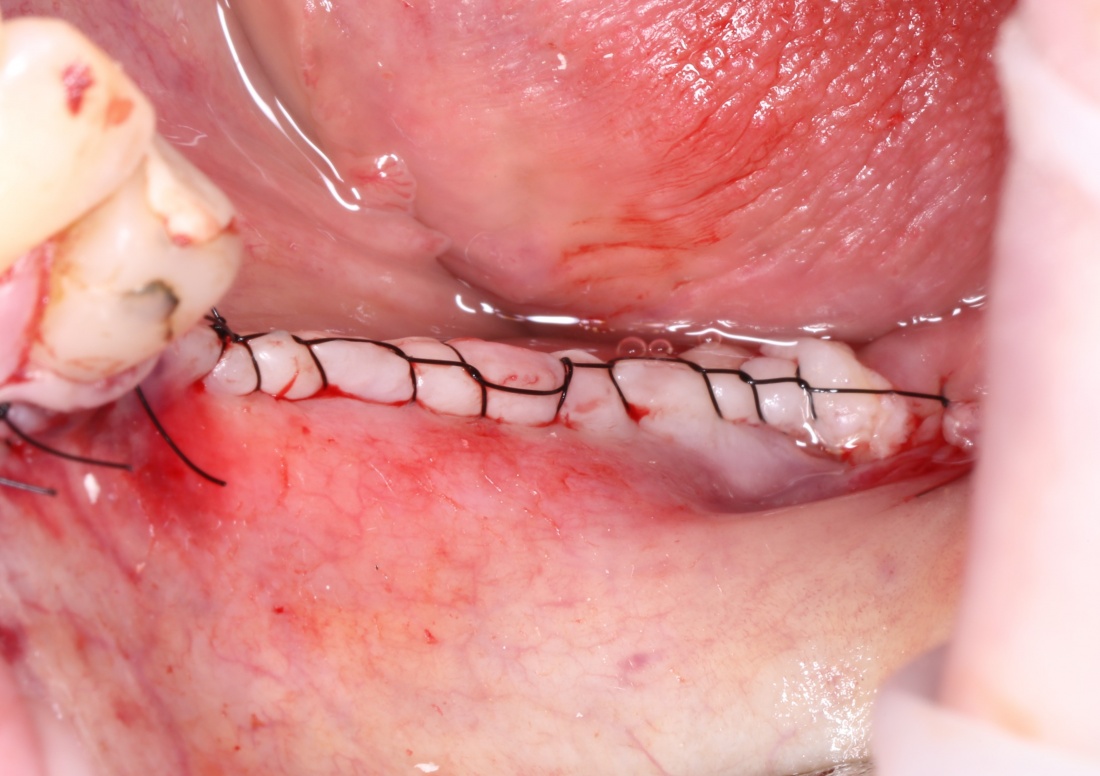

Простой. Надежный. Дешевый. Способ остеопластики.